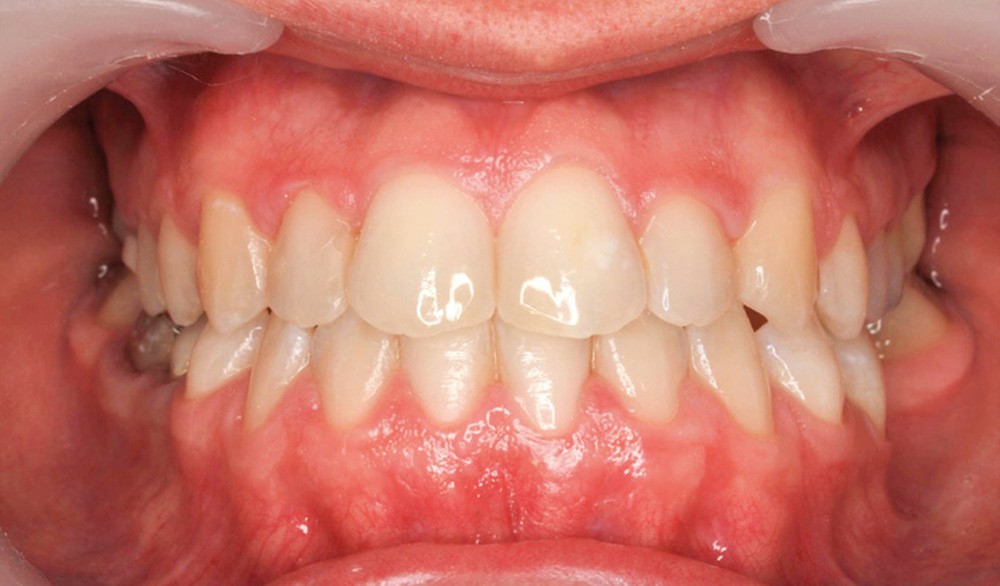

Diagnostic (fig. 1a-g)

La patiente présente une classe III squelettique dans un contexte hyperdivergent associée à une endoalvéolie maxillaire, un articulé inversé antérieur, une rétroversion incisive maxillaire, des rapports de classe I canine bilatérale, une absence de 16 et 36.

Au niveau esthétique, le profil est rectiligne. La lèvre supérieure est plus effacée, en retrait par rapport à la lèvre inférieure. De face et de profil, la mandibule paraît massive et le maxillaire effacé : le manque de soutien de la lèvre supérieure contribue à cette impression.

Le sourire est étroit, dégradé par les malpositions dentaires.